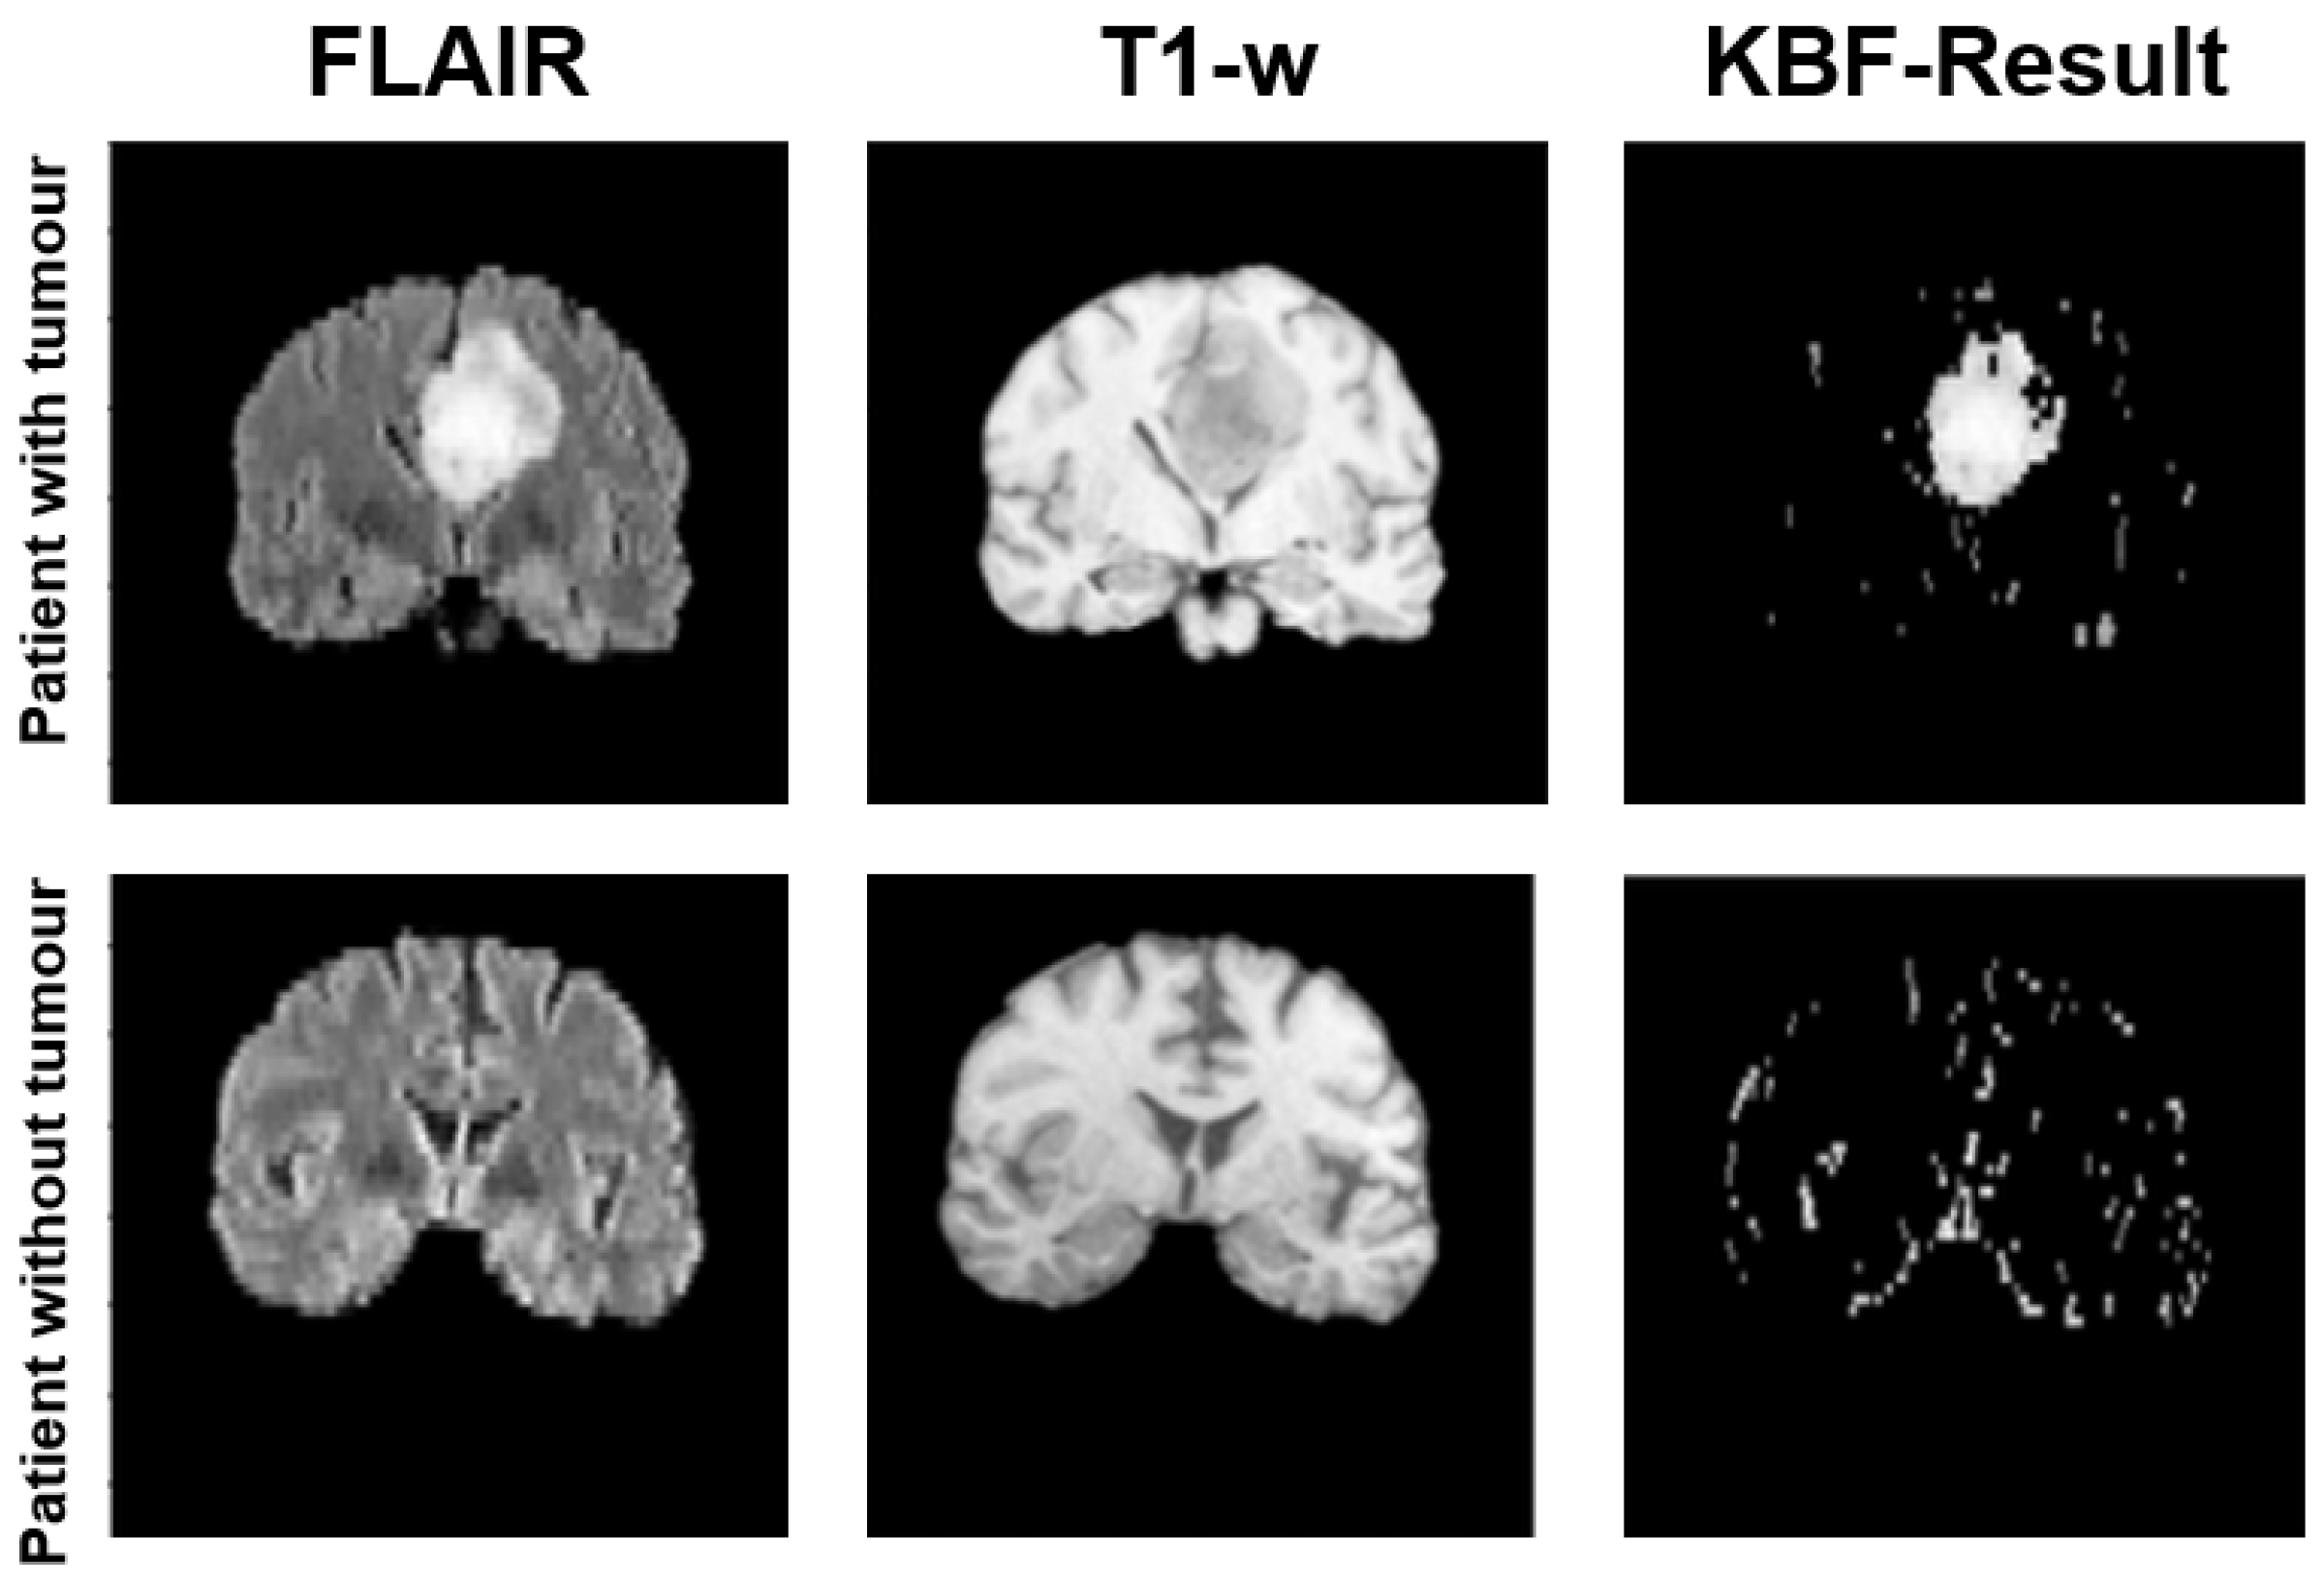

Figure 4.

An illustrative example of the results produced by the KBF module on two patients: if the slice contains a tumor (top row) a huge cluster is generated in the preselection mask, while in the opposite case (bottom row) the mask contains sparse outliers.